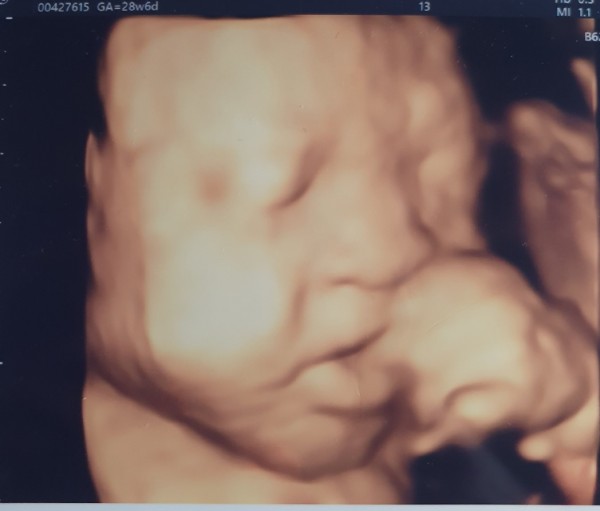

2021-04-30안녕하세요, 경미님. 시험관 시도를 하는 동안 여러 과정 속에서 힘드셨을 마음이 편지를 통해 고스란히 전해지는 듯 합니다. 그러한 시간들을 견뎌 내시고, 어느덧 사진 속 너무도 귀엽고, 사랑스러운 경미님의 아이가 소중한 탄생의 순간을 앞두고 있다는 것이 기적처럼 아름답습니다. 앞으로도 보내주신 마음을 통해 더욱 많은 생명의 터가 되겠습니다. 진심으로 축하드리며, 앞으로 가정내 늘 평안하시고, 행복하세요.